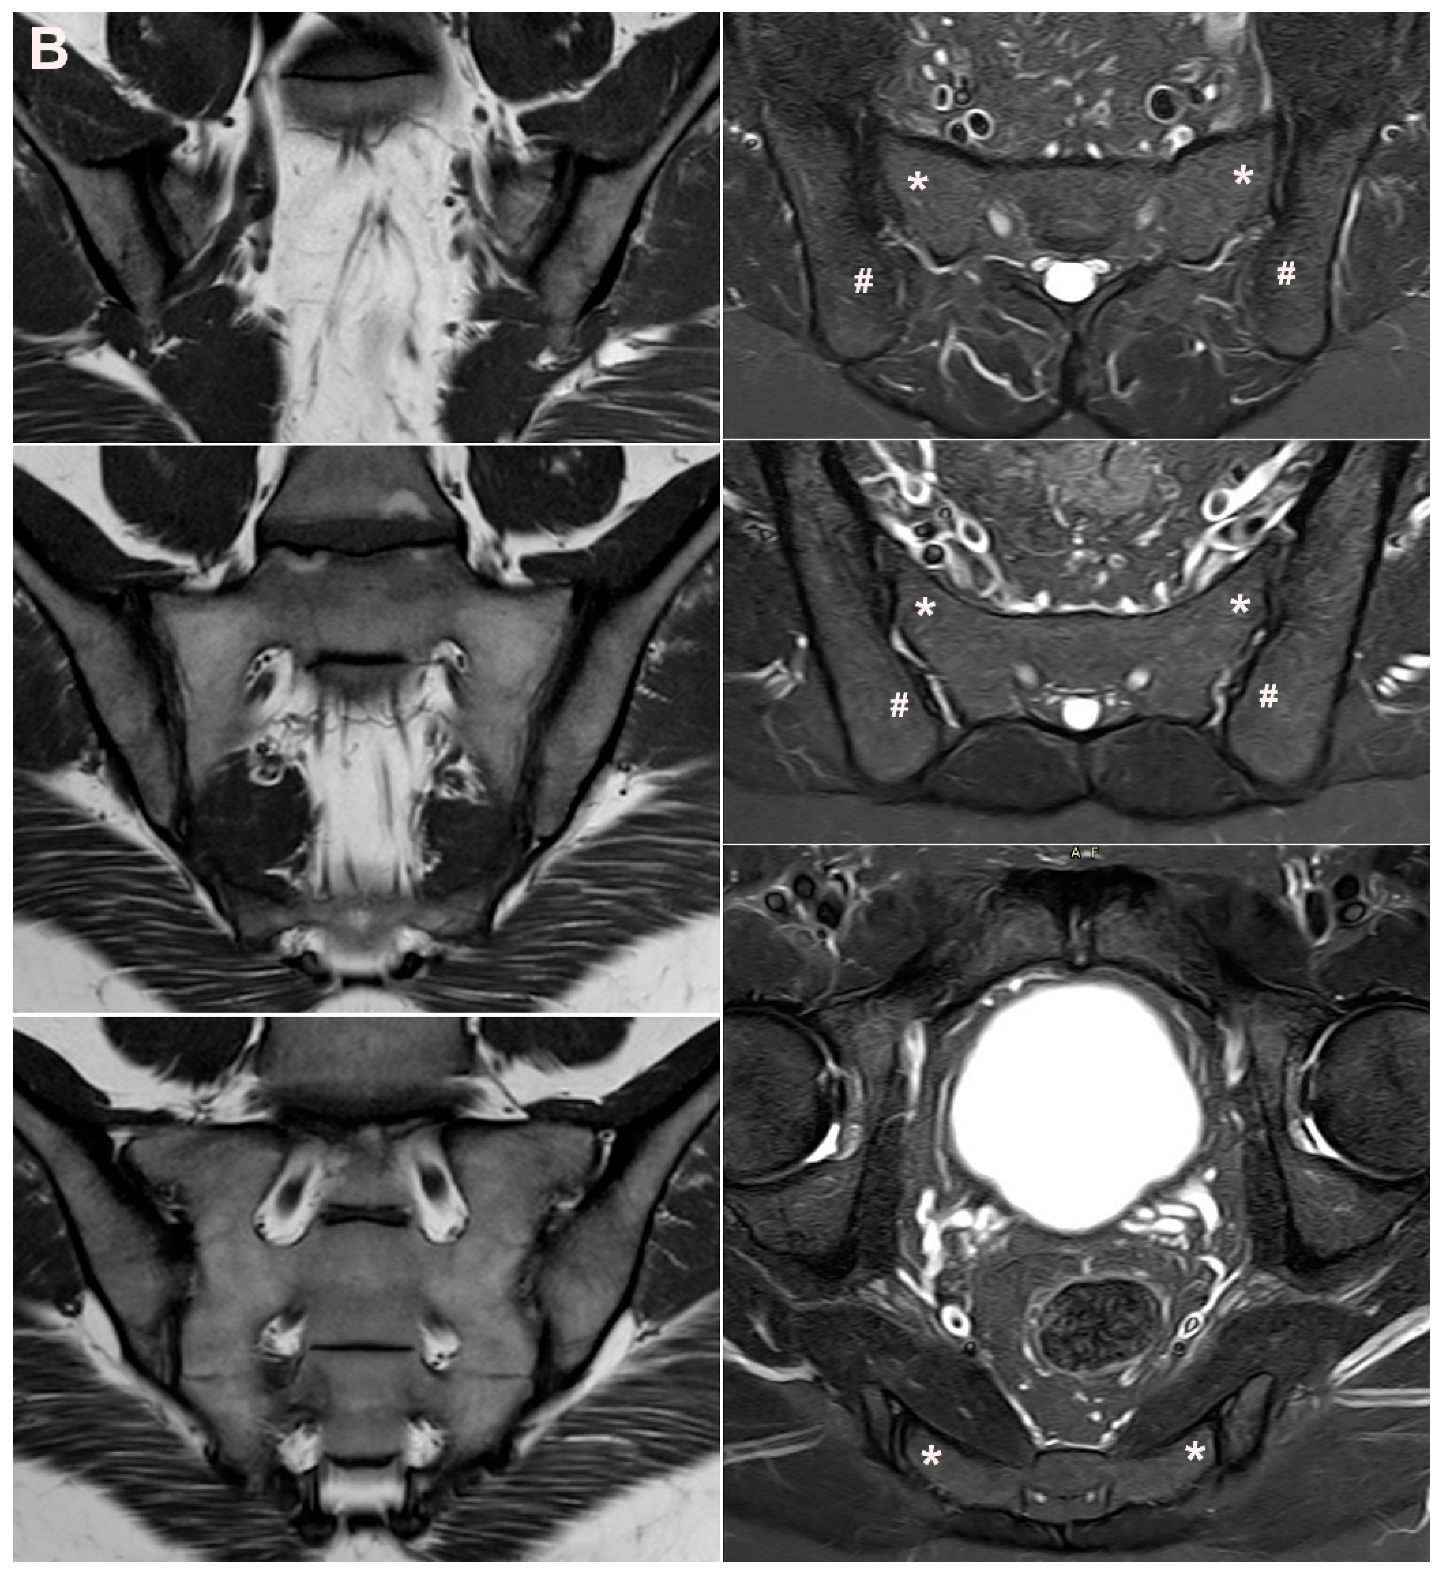

- Kiil, R.M.; Weber, U.; Loft, A.G.; Maimburg, R.D.; Jurik, A.G. Evolution of MRI Lesions at the Sacroiliac Joints during and after Pregnancy by Serial MRI from Gestational Week 20 to 12 Months Postpartum. Arthritis Rheumatol. 2023. accepted. [Google Scholar] [CrossRef]